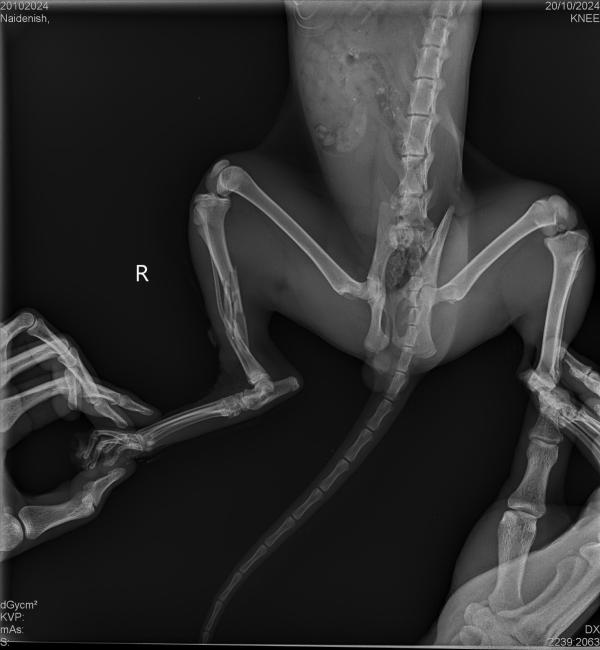

Девочки, помогите пожалуйста вывести в ТОП!!!!!!!!! Подобрали вчера котике на трассе со сломанной лапой. Отвезли в ветклинику. Сделали рентген и подтвердили что лапка сломана. Нужна операция. Уже с утра собрала из 100 тыс 56 тыс. Может есть среди вас неравнодушные к братьям нашим меньшим🙏🏽 Собрать котику на операцию. Все фото и документы прикреплю. Пожалуйста хотя бы с топом помогите 🆘 🆘🆘🆘🆘🆘. Девочки с Момлайф, можете подписать что с приложения, чтобы мне потом отчитаться по собранным средствам😘

@dildildil, говорят грудной отдел тоже пострадал. Поэтому он не может поднять голову. Я и думала почему он всё время в горизонтальном положении. Я же его с рук кормила и поила шприцом. Ждут когда оклемается, потом только операция. Иначе не выдержит наркоз. Деньги перевела на счёт приюта «Ковчег». Говорили что там будет информация вся по котику

Девочки, спасибо большое. Насобирала котику на лечение. Вчера отвезла в клинику Византия. Его должны были прокапать и посмотреть на состояние. Вот к вечеру написали что и грудной отдел пострадал😭 будут смотреть, возможно не сможет даже вставать. Мне приходилось его из рук кормить и поить со шприца. Очень тяжелый случай. Кстати, на операцию насобирала. Благодарю всех и каждого. У вас большое сердце